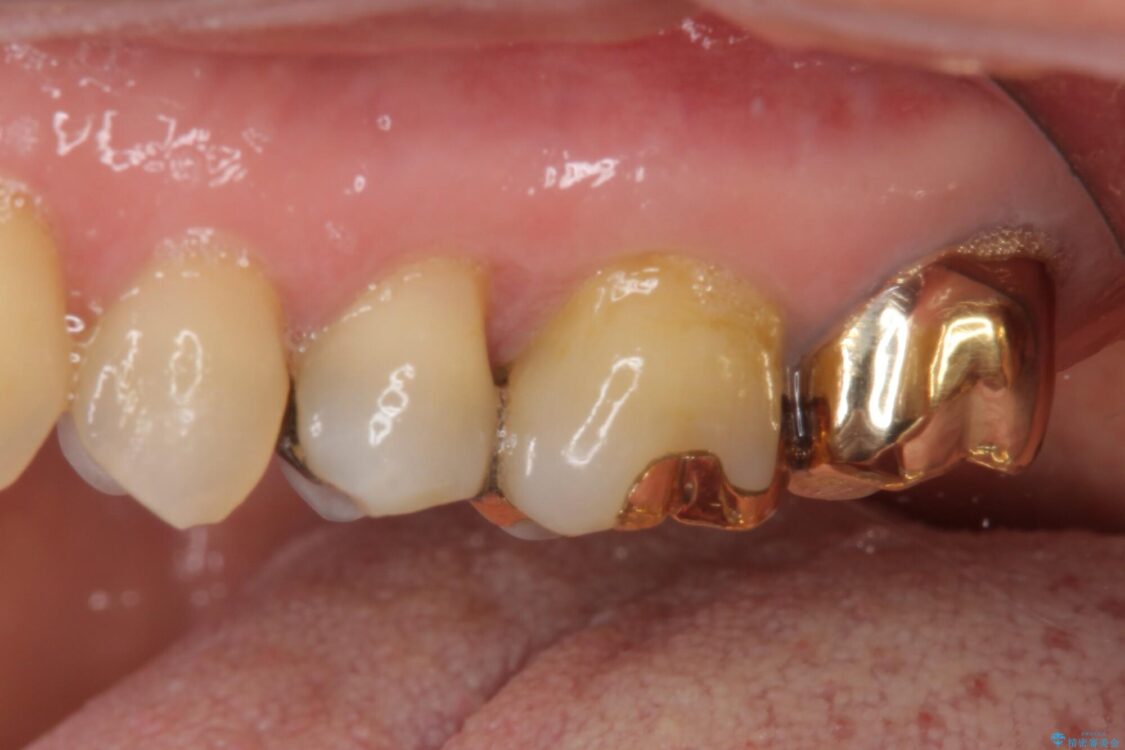

治療後について

正面から見える場所であったため、セラミックインレーで自然な口元にすることができました。

治療後

• 外れてしまった銀歯 セラミックインレーで自然な仕上がりに 治療後画像